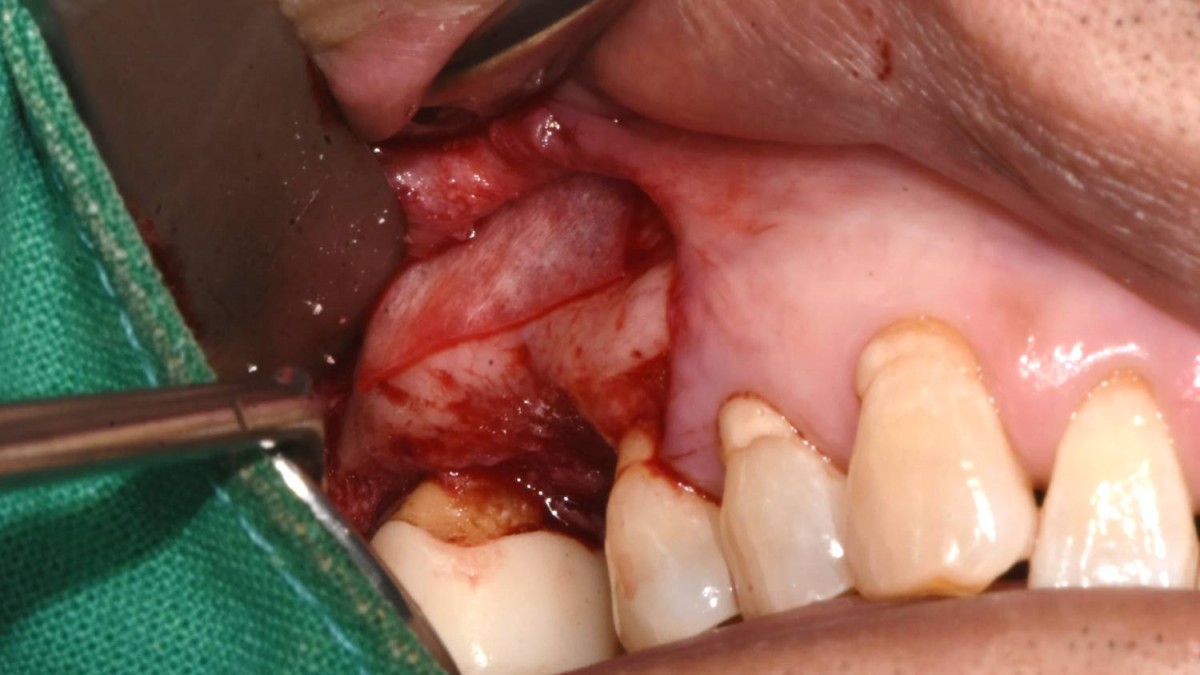

Maxillary Sinus Graft, 2 Implants, Crown Contouring

<GCaks> A 56-year-old male patient had pain-inducing caries, and perio-involved tooth mobility resulted in a tooth fracture at 1st molar. And it was removed months ago. He was a heavy smoker and showed poor oral hygiene.